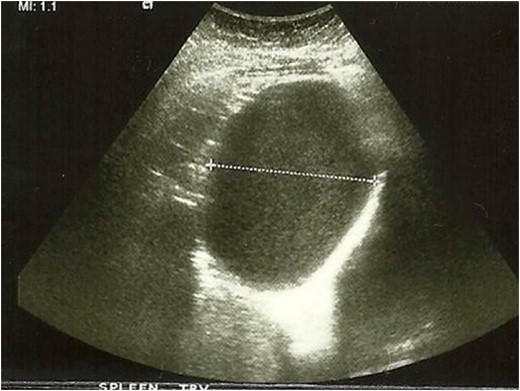

Images from abdominal ultrasound demonstrating the hepatic cyst.

On ultrasonography, they appear as small intra-hepatic lesions with mixed echogenicity [5]. They often appear as target lesions, with central hyper-echogenicity due to cholesterol crystals precipitating out of solution within the dilated BD [6]. On CT scans, VMCs appear irregular with low attenuation areas that do not enhance normally with contrast [5].